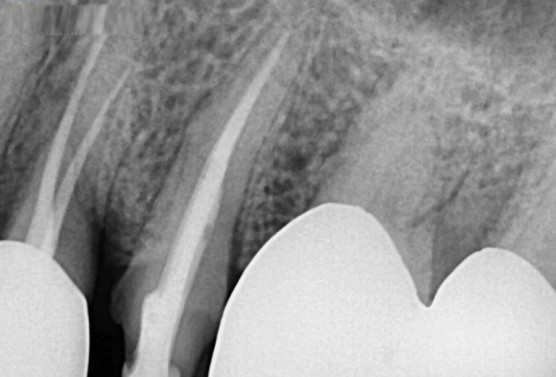

[치료 도중 치아 사진]

치료도중 사진입니다. 치아 내부 깊숙이까지 파절선이 이어진걸 확인할수 있습니다.

[신경치료가 잘 마무리 된 모습]

2번째 오셨을 때 신경치료를 잘 마무리하고,

증상도 호전되셔서 이쁘게 잘 씌워드리고 치료를 마무리 하였습니다.